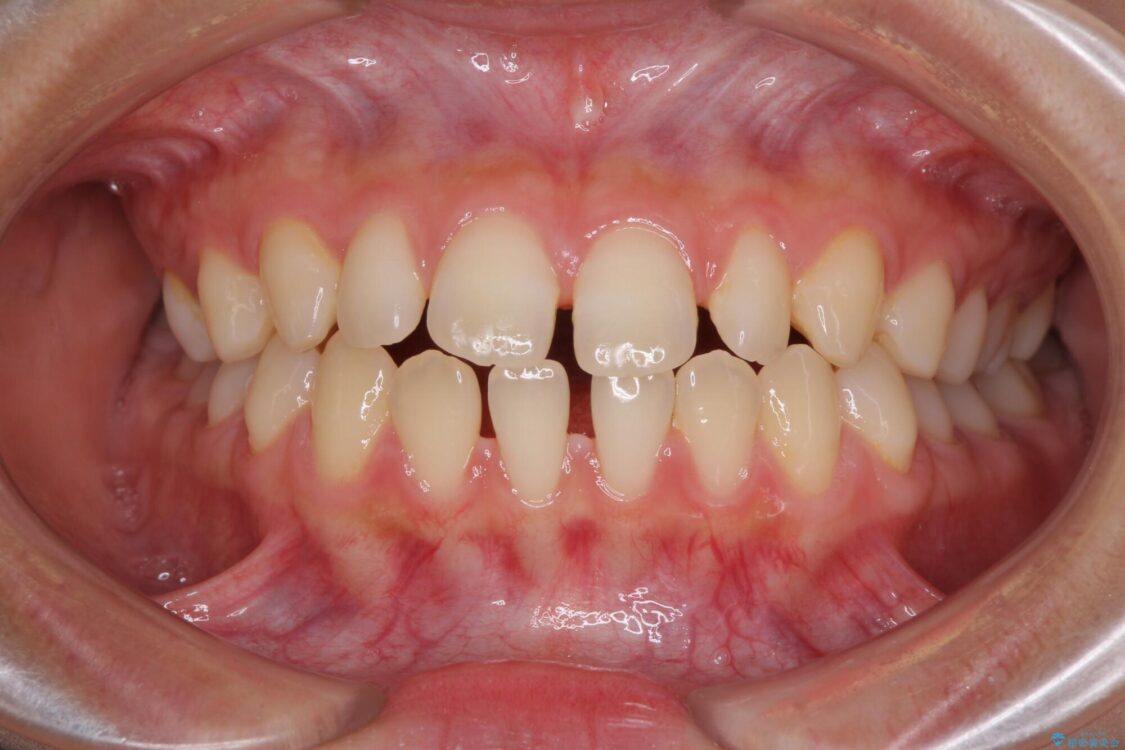

治療前

• 隙間だらけの歯列 インビザラインで改善 治療前画像

前歯の上下スペースと前歯の隙間を気にして来院された患者様です。

飲み込みや話をするときに舌を突出させる癖が強くあり、それが原因でスペースが空いていました。

舌癖を改善するためのトレーニングを行いながら、インビザラインにより上下の前歯の隙間を閉じていくこととしました。